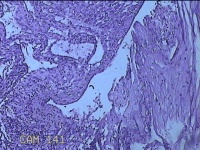

胎盘组织

孕2产39周LOP剖宫产单活胎男婴 剖宫产术

停经39周,下腹胀痛1小时。

灰白暗红色胎盘组织18x16x2.8㎝一个,表面光滑,血管清晰,颜色发暗,绒毛面结节状,轻度糜烂,表面有少许凝血块,切面见绒毛内有部分淤血,边缘蜕膜可见多个小血肿,脐带21.5x2x0.8㎝,切断脐带,见脐血管内有凝血块。